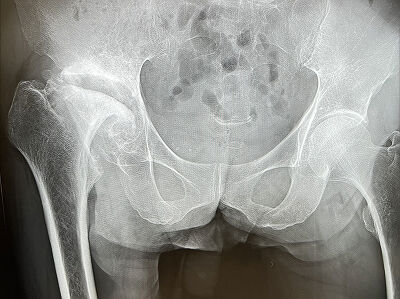

↑↑↑

両側股関節が入ってる画像

これ見ると、どんな病気だかがわかりやすいと思います。